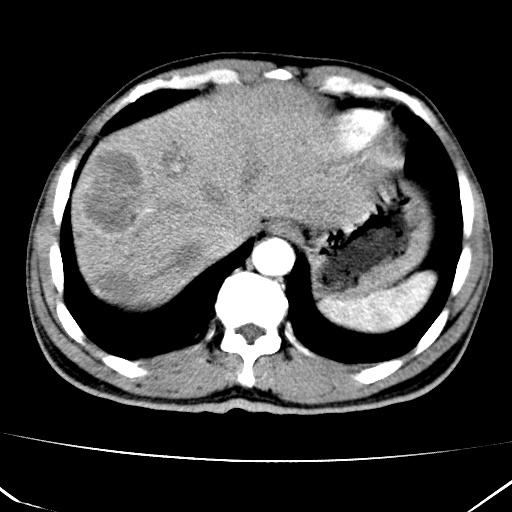

标题: CT17975:请求会诊。男、57岁。上腹部胀痛2天。临床诊断:糜 [打印本页]

标题: CT17975:请求会诊。男、57岁。上腹部胀痛2天。临床诊断:糜

肝脏多发类圆形低密度影,考虑肝脏转移瘤,肝胃韧带一淋巴结肿大,原发?胃癌?

考虑胃癌并肝脏及腹膜后淋巴结转移;不排除淋巴瘤。

肝内转移瘤,腹腔及腹膜后淋巴结转移。